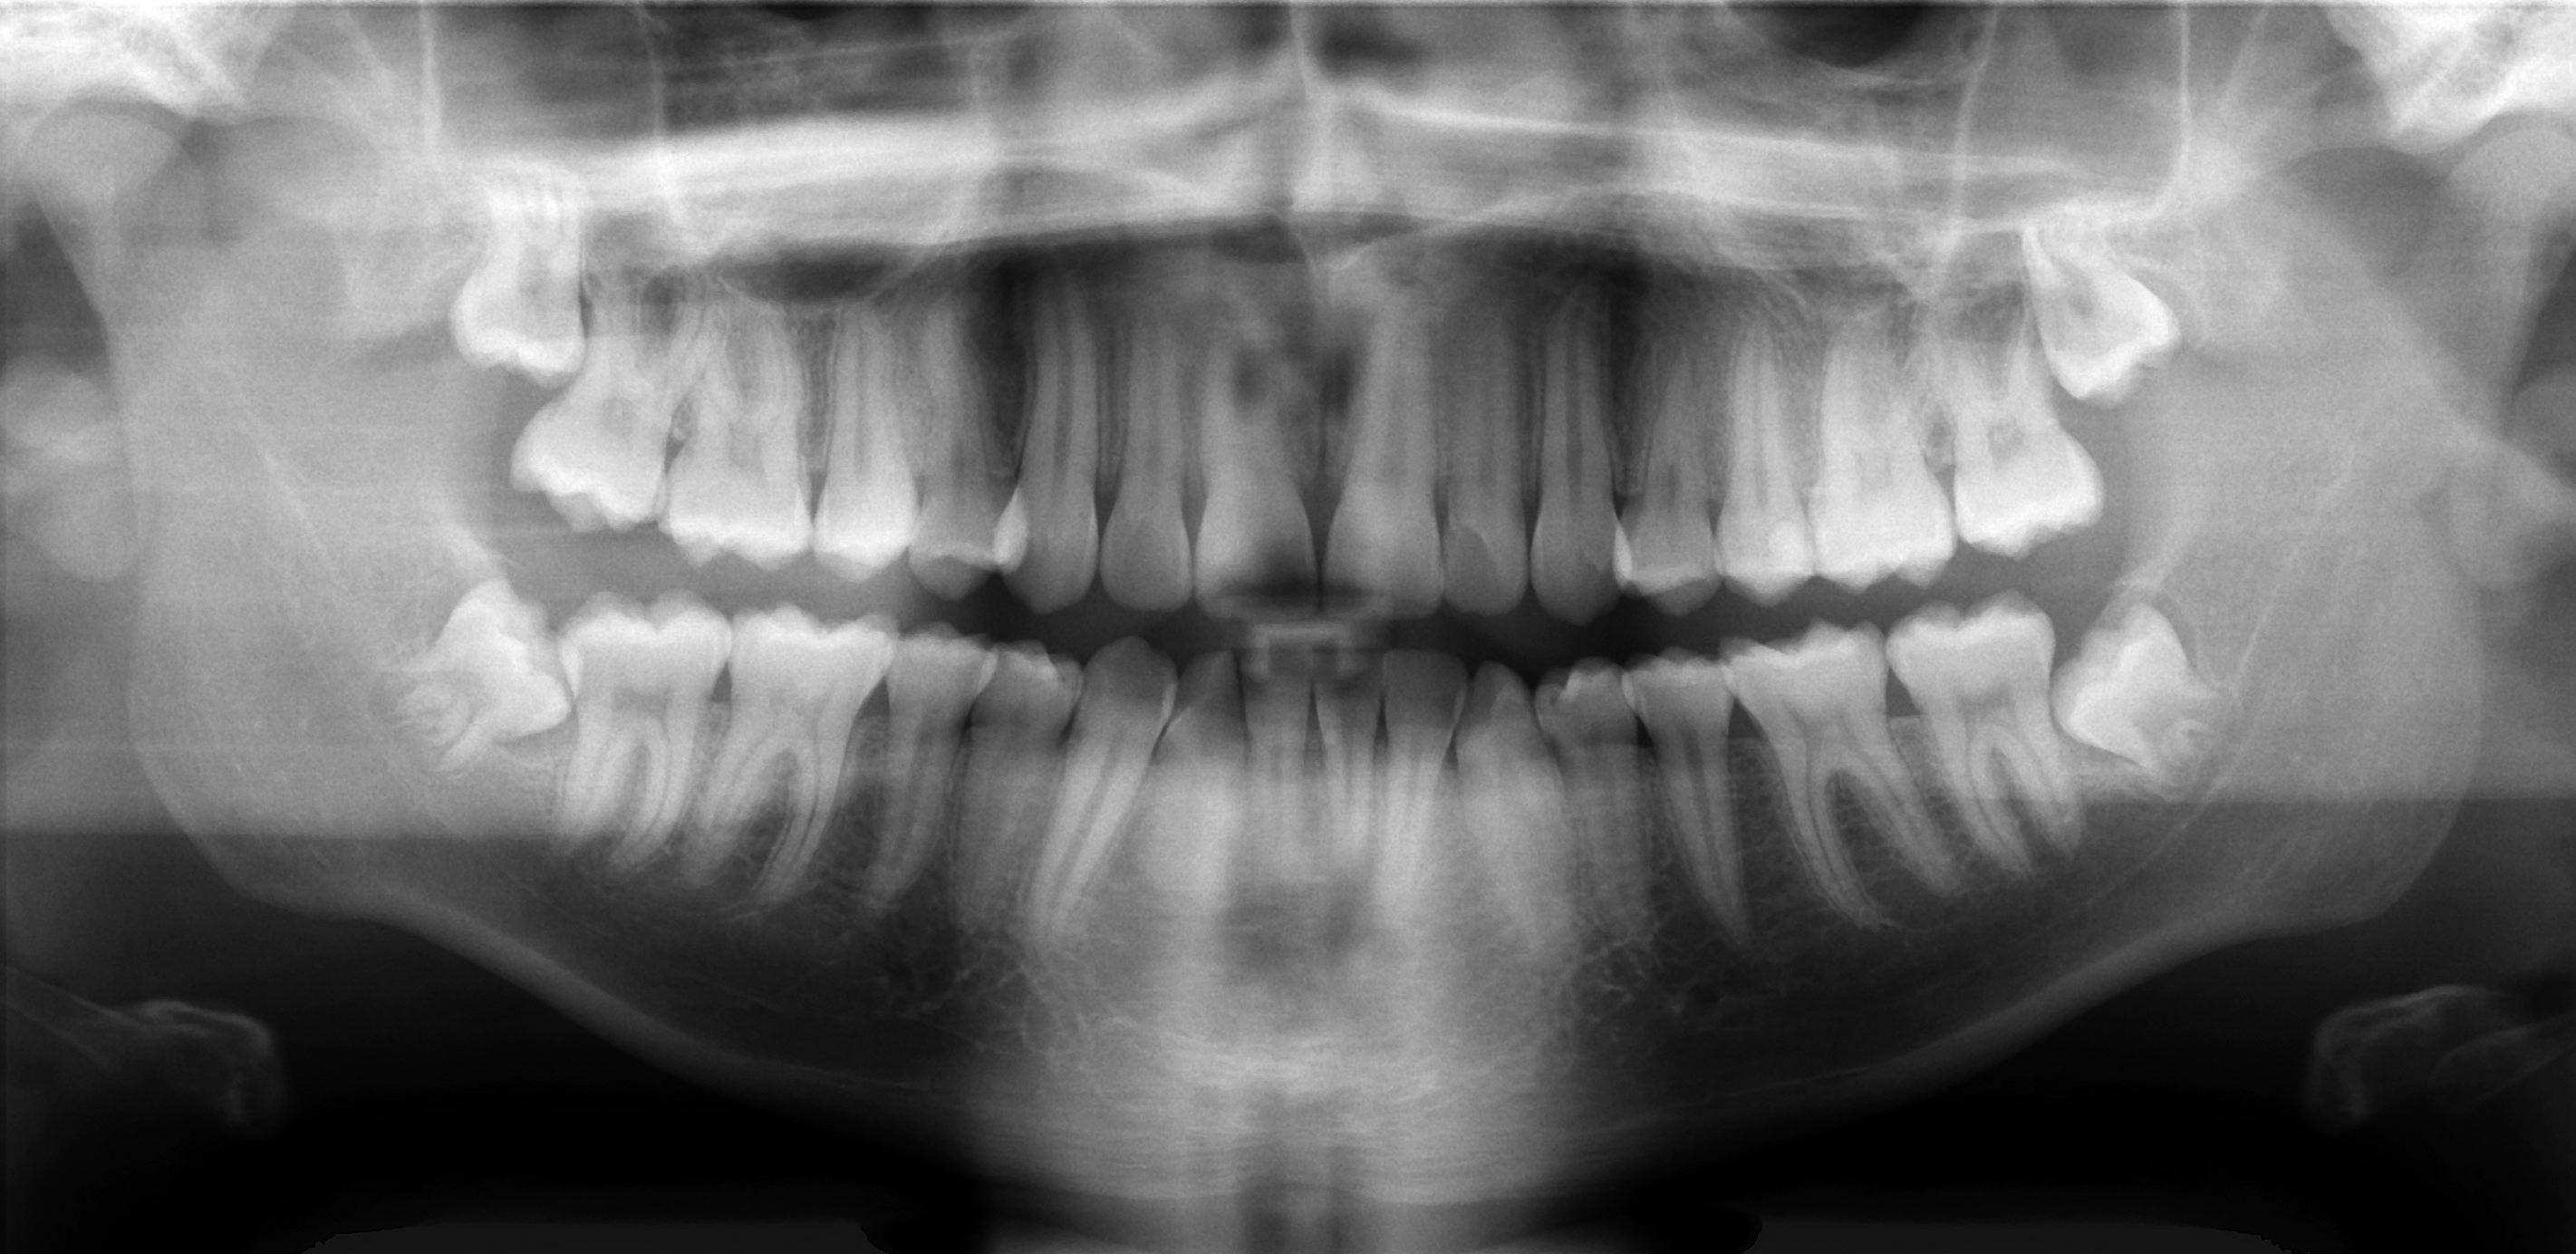

However, in these two cases, and an unknown number of others, these minors were taken in handcuffs by Immigration and Customs Enforcement (ICE) and held in adult detention facilities. The reason? In the absence of other information that could corroborate the teens’ self-reported ages, analysis of their dental X-rays revealed that both could be adults.

As a forensic anthropologist, I support these judicial decisions. My work can include estimating the ages of deceased persons using X-rays of bones and teeth, and I’m intimately familiar with the limitations of how specific these techniques can be. In my field, we generate an age range alongside several caveats; it’s irresponsible for ICE to rely solely on X-rays to provide a definitive answer in determining if a person is a minor or an adult.

For children and teenagers, such an analysis can be carried out by examining X-rays. Growth and development are predictable processes, and milestones occur in a particular order. This is the reason that a tooth such as the first adult molar is also known as the “six-year molar,” because it generally erupts in everyone around age 6, give or take.

The analysis proceeds the same way whether we’re examining the X-rays of a living or deceased person. Essentially, we compare the stage of growth shown in the X-ray to existing growth charts from children and teenagers of known ages.

The crucial point is that it’s not possible to make a definitive, single age determination from X-rays or examination of bones or teeth. A variety of factors affect how well chronological age corresponds with biological age; that is, the amount of time since birth doesn’t necessarily correlate to the exact same stage of growth in every child or teenager.

Sometimes, the estimated age range might include ages below and above 18. Take the development of the wisdom tooth, something we often look at when estimating age of older teenagers and young adults. But the development of this tooth is extremely variable, ranging from never developing at all to erupting anywhere from the mid-teens to early 20s. In such cases, how would a final decision of adult or minor status be made?